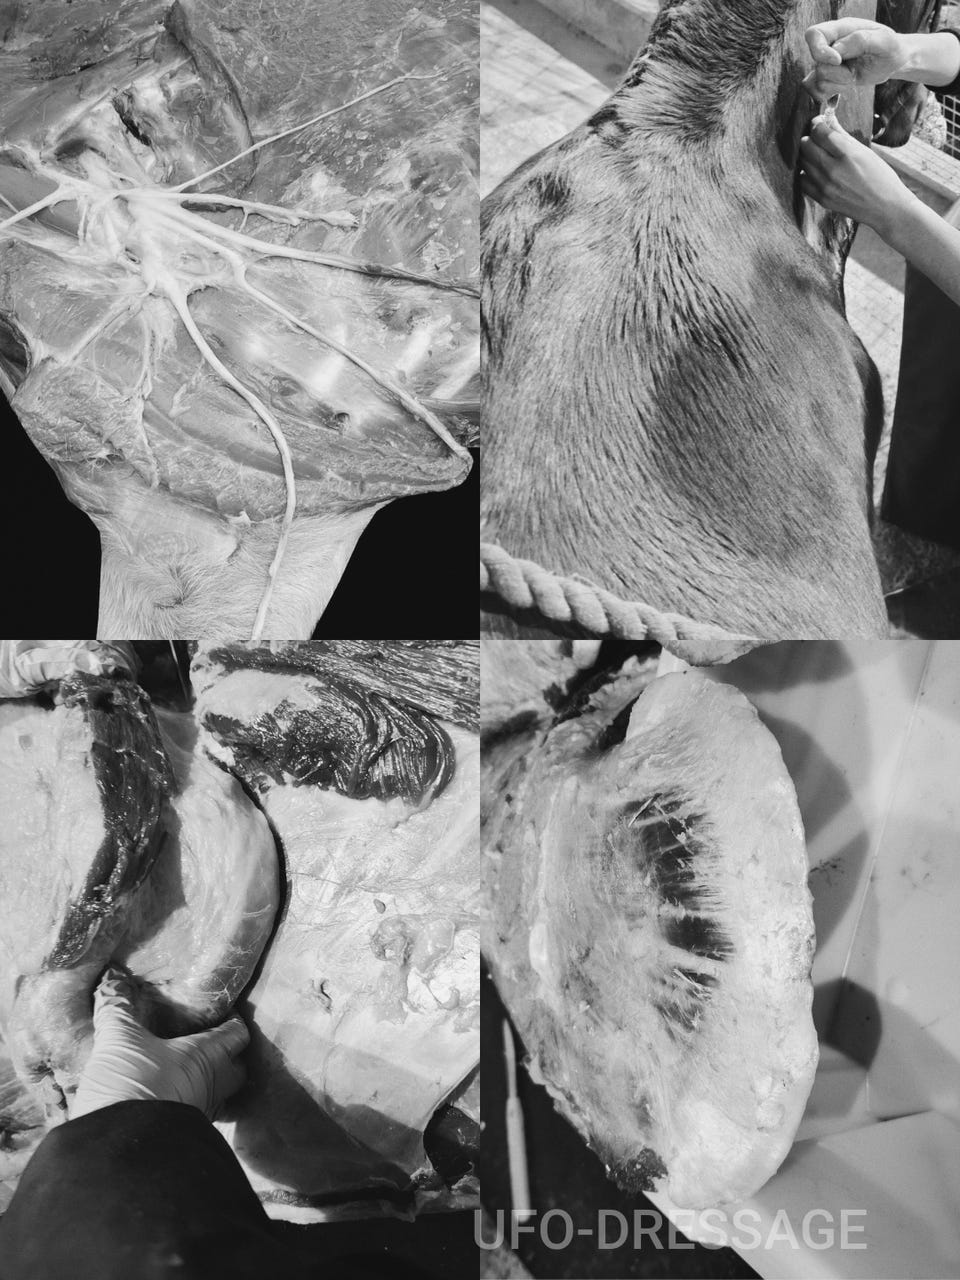

Skader påført av utstyr- mer utbredt enn man tror.

Symptomer på skader kan være diffuse og vanskelig å ‘pin -pointe’ til utstyret.

Hesten kan begynne å vise motvilje mot å legge seg ned, kvier seg for å gå i nedoverbakker, eller får kortere steglengde. Subtil til tydelig halthet, protester ved påsalig, under rytter (ofte i gallop og eller over hinder) og kan vise tegn til muskelatrofi (musklene bak skulderbladet svinner hen).

Å Forebygge disse skadene bør prioriteres, og kan gjøres med enkle grep i form av god nok og korrekt padding av utstyret. For å forebygge bør utstyr paddes godt og korrekt opp for de utsatte områdene, sørg også for at utstyret tilpasses MED padding på.

Vet. Sofie Jubskås, holdbarhest.no

Celine A. Leviathana, ufodressage.no

Fotograf Ada Marlene Vrolijk